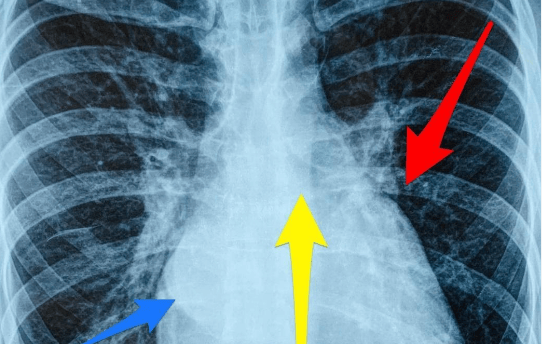

Insuficiência Cardíaca Congestiva (ICC):

Condição na qual o coração não consegue bombear sangue suficiente para atender às necessidades do corpo. Pode resultar em acúmulo de fluido nos pulmões e nos tecidos, causando dificuldade respiratória e inchaço.